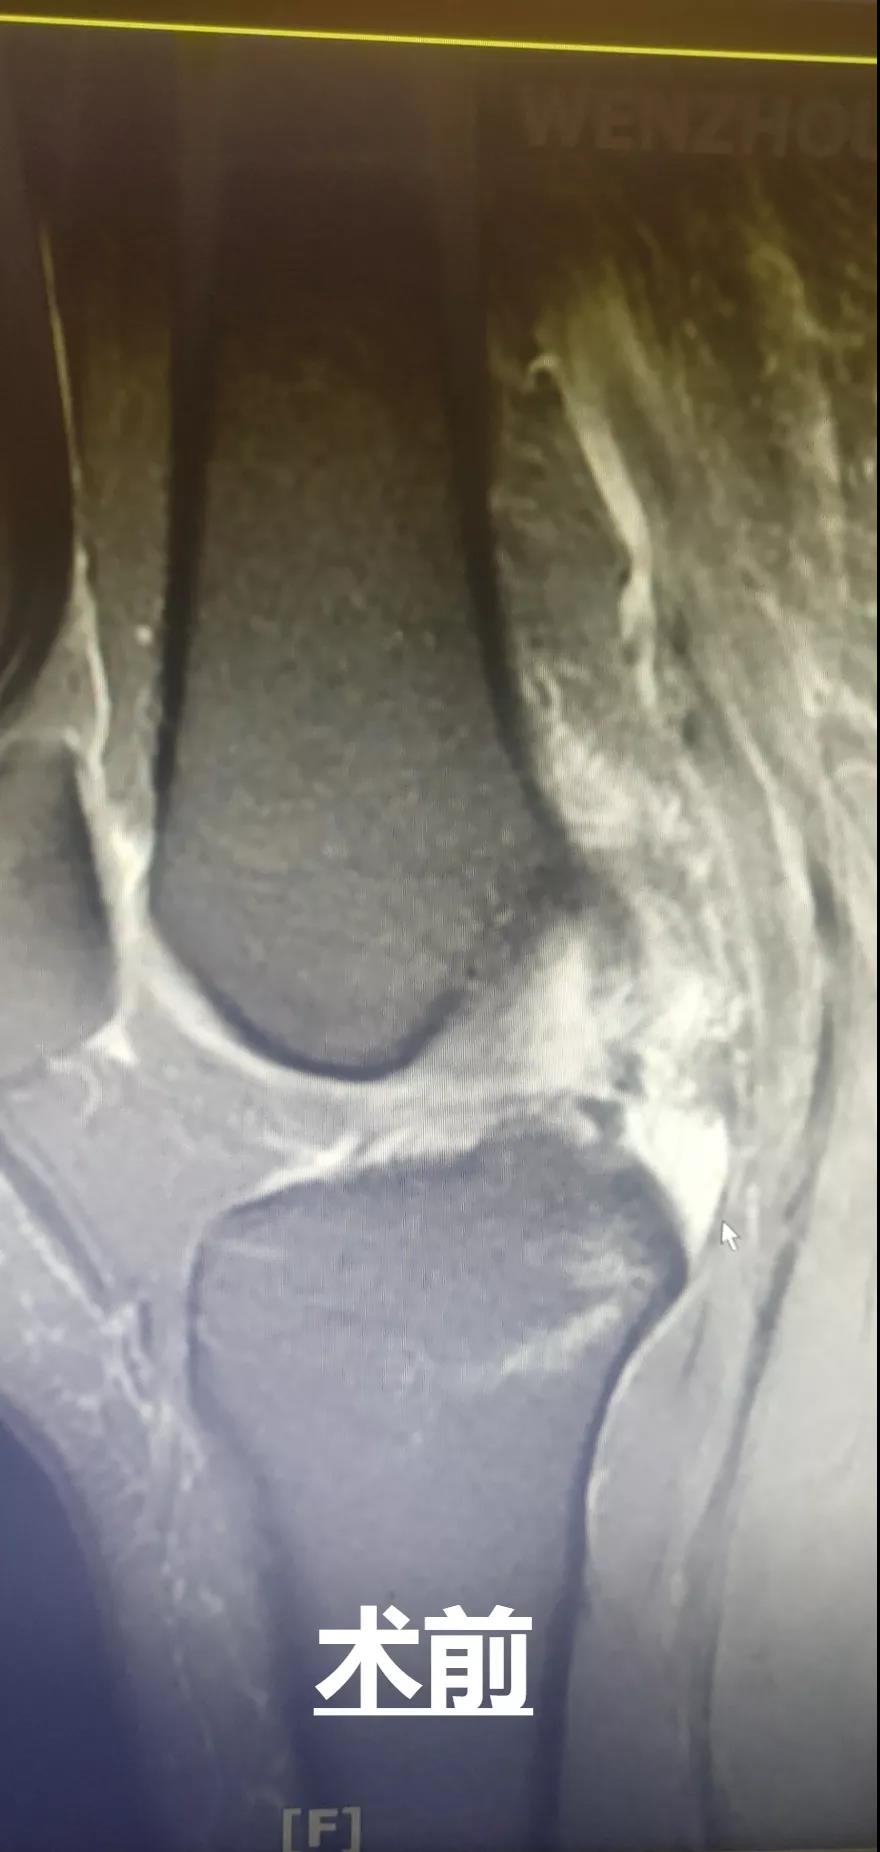

此外,和平國際醫院關節鏡微創團隊還完成了一例交叉韌帶修復術。此手術采用三個約0.5cm的微小創口,于脛骨結節處進行定位,后鉆通脛骨隧道,應用多種袢鈦板進行多位置固定,手術過程短,創口小,術后效果好,患者十分滿意。